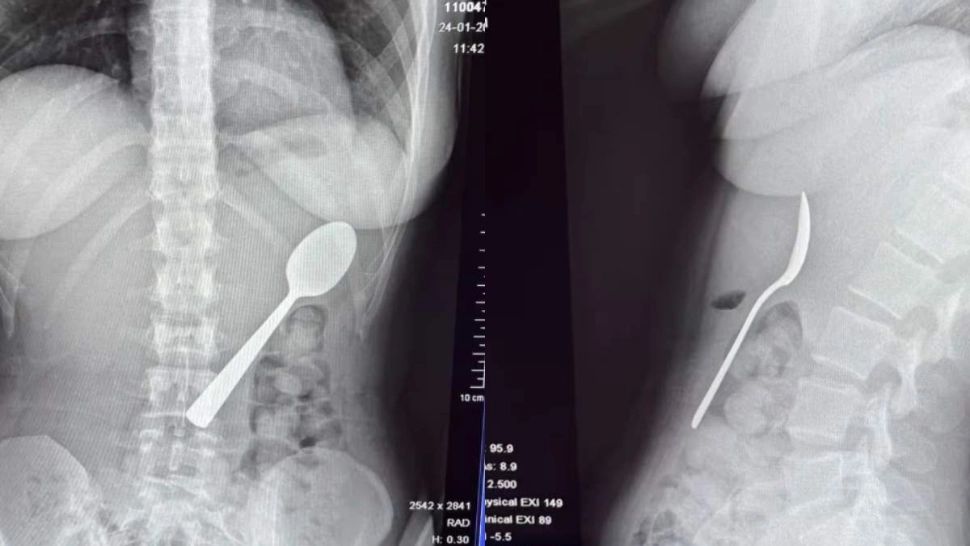

O tânără de 28 de ani a trecut printr-o experiență periculoasă și rar întâlnită: a înghițit accidental o lingură lungă de 17 cm în timp ce mânca iaurt acasă. Incidentul s-a produs după ce câinele său a sărit brusc în poala ei, provocând o reacție neașteptată.

Reymy Amelinckx a povestit că stătea pe canapea și mânca iaurt, ținând lingura în gură pentru a avea mâinile libere să răspundă la un mesaj. Câinele său, un vizsla maghiar pe nume Marley, a sărit peste ea, iar surpriza a făcut ca lingura să alunece în gât. „Am fost atât de surprinsă încât mi-am dat capul pe spate și, înainte să realizez ce se întâmplă, lingura era deja în stomac. A trebuit să aleg între a mă sufoca sau a o înghiți”, a explicat tânăra.

Inițial, ea a încercat să scoată lingura cu mâna, dar situația s-a dovedit prea rapidă și periculoasă. Abia după câteva ore și după ce simptomele: balonare, grețuri și dificultăți la masă, au persistat, tânăra a decis să meargă la spital.

Două zile mai târziu, lingura a fost îndepărtată sub anestezie locală, fără a fi necesară o intervenție chirurgicală deschisă. Procedura a implicat rotirea lingurii în stomac, ceea ce a cauzat o mică hemoragie gastrică, însă tânăra a declarat că s-a simțit imediat ușurată după finalizarea procedurii.

Reymy a fost externată câteva ore mai târziu și a început să se recupereze rapid. Ea a menționat că a resimțit dureri temporare în gât din cauza leziunilor esofagului, precum și episoade minore de sângerare gastrică și sensibilitate stomacală, însă nu au fost afectate funcțiile digestive pe termen lung.